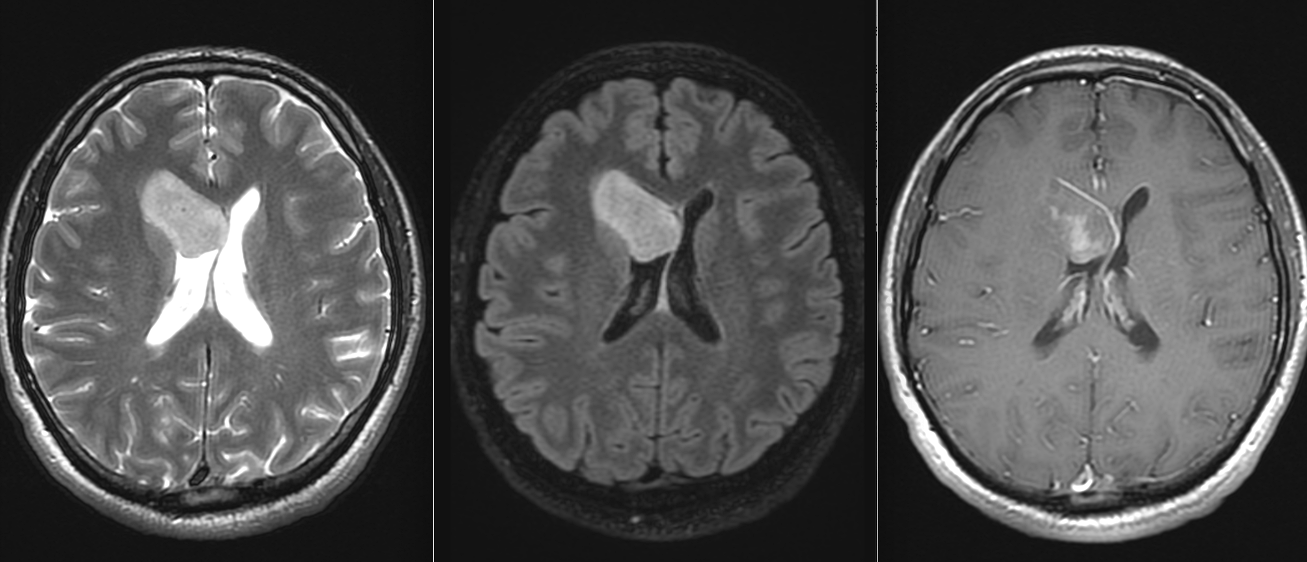

Supratentorial – mai des întâlnit la adulți – în ventriculii laterali sau în ventriculul III (pe linia mediană).

Ependimoamele supratentoriale:

Convulsii

Hemipareză

Tulburări cognitive

Asimptomatice de multe ori – descoperite întâmplător

RMN cerebral și/sau spinal cu gadolinium este standardul de aur. Tumorile apar ca mase bine delimitate, care pot conține chisturi și zone de necroză. Adesea pot conține microcalcificări (vizibile mai bine pe CT). Datorită localizării intraventriculare, ependimoamele pot determina obstrucția circulației lichidului cefalo-rahidian și hidrocefalie.

Pentru pacienții care nu pot efectua RMN, tomografia computerizata (CT) este utilă, dar tumorile de mici dimensiuni pot trece neobservate.

Diagnostic diferențial

Ependimoamele trebuie diferențiate de alte tumori cu localizare ventriculară sau în fosa posterioară:

Meduloblastom

Astrocitom pilocitic

Metastaze

Tumori neuroectodermale primitive

Papilom de plex coroid

Diagnosticul diferențial se face pe baza imagisticii, histologiei și, tot mai important, pe profilul molecular.